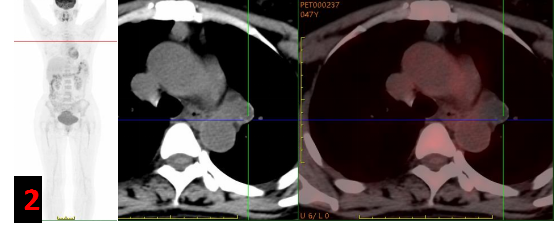

PET/CT?

主動脈弓左旁不規(guī)則混雜密度腫塊影,邊緣見斑點(diǎn)狀/環(huán)形鈣化灶,F(xiàn)DG代謝不高(SUVmax約0.3-1),考慮良性病變(圖2)。